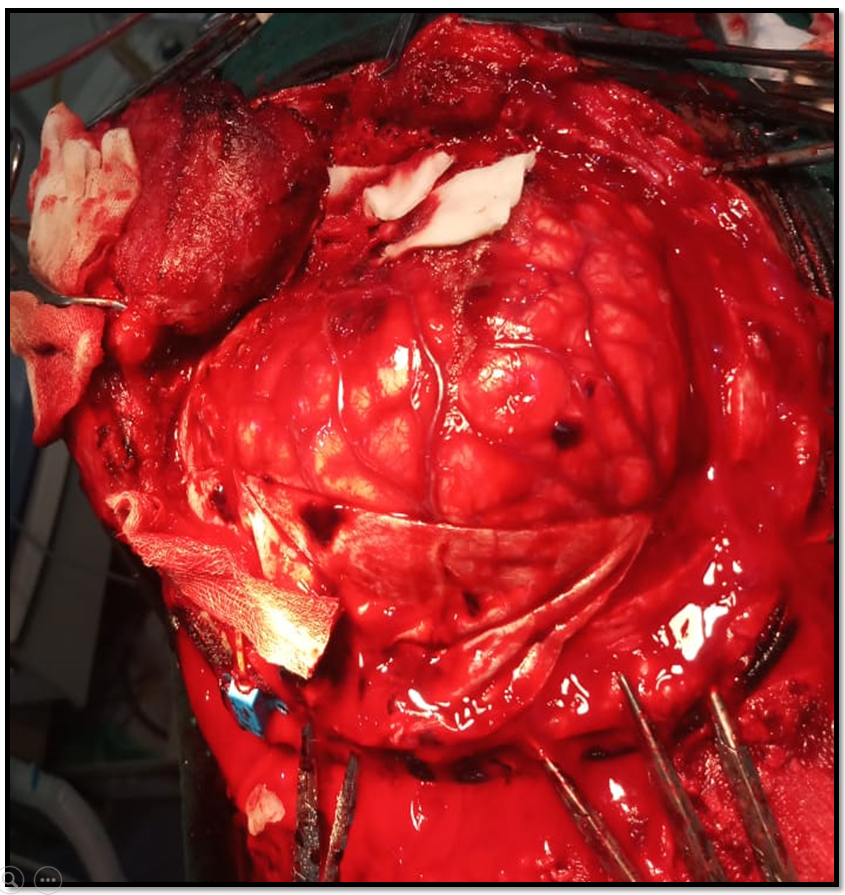

As per our protocol ICP surge greater than 25mmHg, resistant to conservative therapy, decompressive craniotomy was planned.

Upon lifting the bone flap there is a minimal drop in both values but still in high range.

As durotomy is done, both ICP and ICP A again plummet to the normal values, also evidenced by the graph.